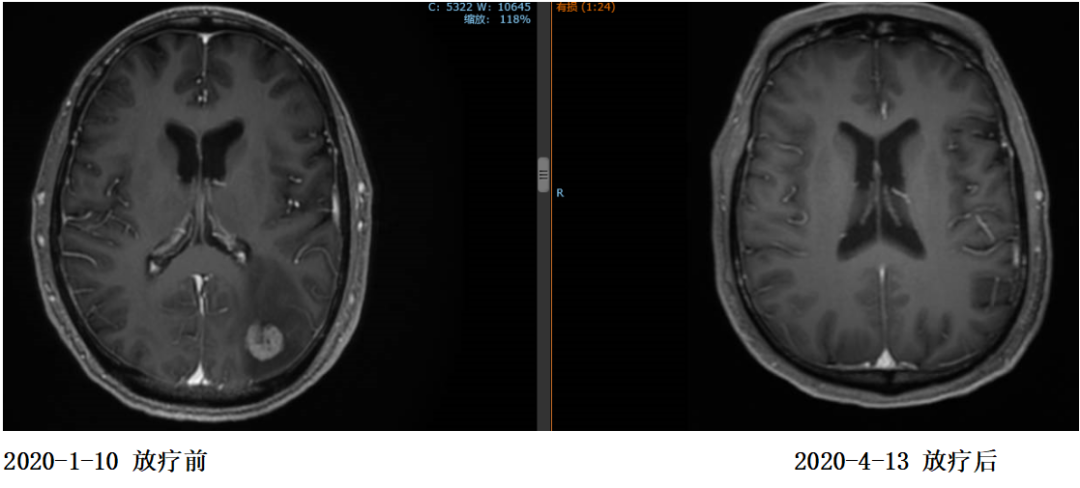

2020年1月患者出现头痛症状,复查脑MR示:枕叶及右侧小脑半球多发结节,结合病史考虑转移灶。

2020年1月13日开始对左侧枕叶及右侧小脑转移灶进行放疗,PTV-GTV=44.5Gy/9F

复查:2020.4复查颈部CT及全腹部+盆腔MR大致同前,脑MR示病变较前明显缩小,评估PR。

2020年11月4日复查颈部胸腹盆CT大致同前,脑转移灶明显缩小,继续赫赛汀联合希罗达维持治疗。